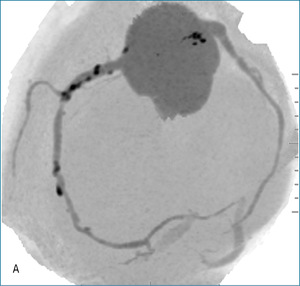

Rycina 3. Badanie tętnic wieńcowych metodą koronarografii. A. Pień LTW – bez zwężeń, gałąź przednia zstępująca (GPZ) – po oddaniu gałęzi diagonalnej subtotalne zamknięcie, na obwodzie istotne zwężenie. B. Prawa tętnica wieńcowa – dwa istotne zwężenia w segmencie 2 i 3.

W koronarografii odnotowano następujące wyniki: pień LTW bez zwężeń, gałąź przednia zstępująca – po odejściu gałęzi diagonalnej (D1) subtotalne zamknięcie, na obwodzie istotne zwężenie, D1 – w ujściu zwężenie krytyczne; gałąź okalająca – dwa istotne zwężenia w odcinku początkowym i środkowym, prawa tętnica wieńcowa – dwa istotne zwężenia w segmencie 2 i 3 (ryc. 3).